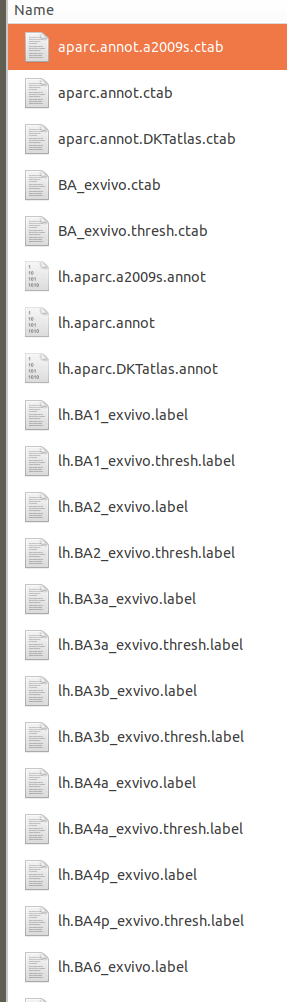

在label文件夹中,

有.ctab文件,表示分割完后的颜色信息(RBG):

还有相同文件名对应的.annot文件,在网站中也有说明:

上图不同的分割分到的结果不一样,有的分的细,有的分的粗。还可以利用第三方的库,作为新的分割模板。

还有 .label文件,上图中每一个颜色块都是一个label .